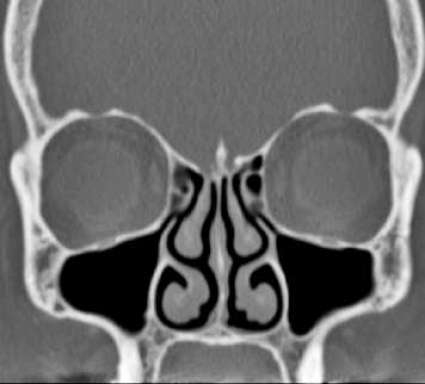

Endoskopik sinüs cerrahisi kararı hastanın klinik yakınmaları ve endoskopik burun içi muayenesi ile alınır. Sinüs tomografisi de anatomik ilişki ve komşulukları ve hastalığın yayılımını görerek cerrahi güvenliği sağlamak için, genellikle uygun bir tıbbi tedaviden sonra istenilir. Yalnız başına tomografi ile ameliyat kararı genellikle verilemez. Ameliyathanede hastanın tomografisine gerek vardır. Ameliyat sonrası hasta izlenimi ise endoskopik muayene ile yapılır, tomografik incelemeyi tekrarlamaya bazı özel koşullar dışında gerek yoktur.